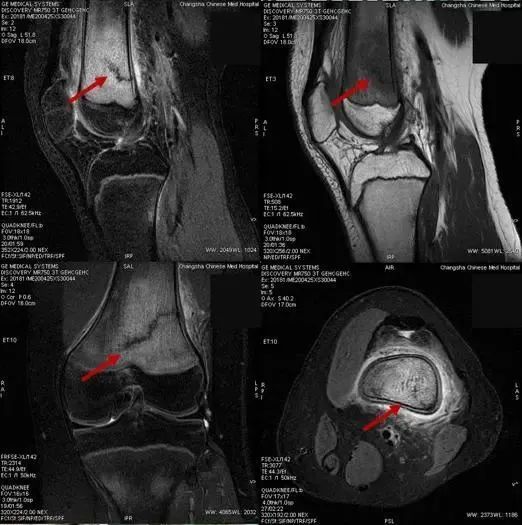

4月27日,湖南长沙市中医医院(长沙市第八医院)放射科 MR 技术组长周飘华与正在阅片的医师陈婷婷讨论。

近三天来,科室陆续诊断了7例“应力性骨折”患者,这7名患者有一个共同点:都是14~15岁的青少年。

15岁的罗同学,因“右膝关节肿痛,加重1天”入院,在行膝关节磁共振成像检查时,发现“右侧股骨下段骨折并广泛骨髓水肿”。

通过仔细询问病史发现,这名疫情期间新近返校的初三学生,因邻近中考需要参加体育考试,每天都进行了一定强度的体育训练,最近几天出现膝关节疼痛明显加重,于是罗同学妈妈带他到医院就诊。

无独有偶,很快,又有三名同学陆续来院就诊,他们的情况与罗同学完全一样,都是14~15岁的初中生,在学校参加跑步等体育锻炼后出现膝关节疼痛,并加重后就诊,经磁共振成像检查,被诊断为应力性骨折。

应力性骨折通过普通X线片往往无法发现问题,容易发生漏诊,需要结合病史、查体,并配合磁共振检查来确诊诊断。